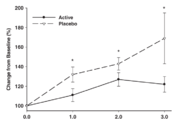

종근당바이오, 2026 한국피부비만성형학회서 티엠버스·티엠버스 N 선봬